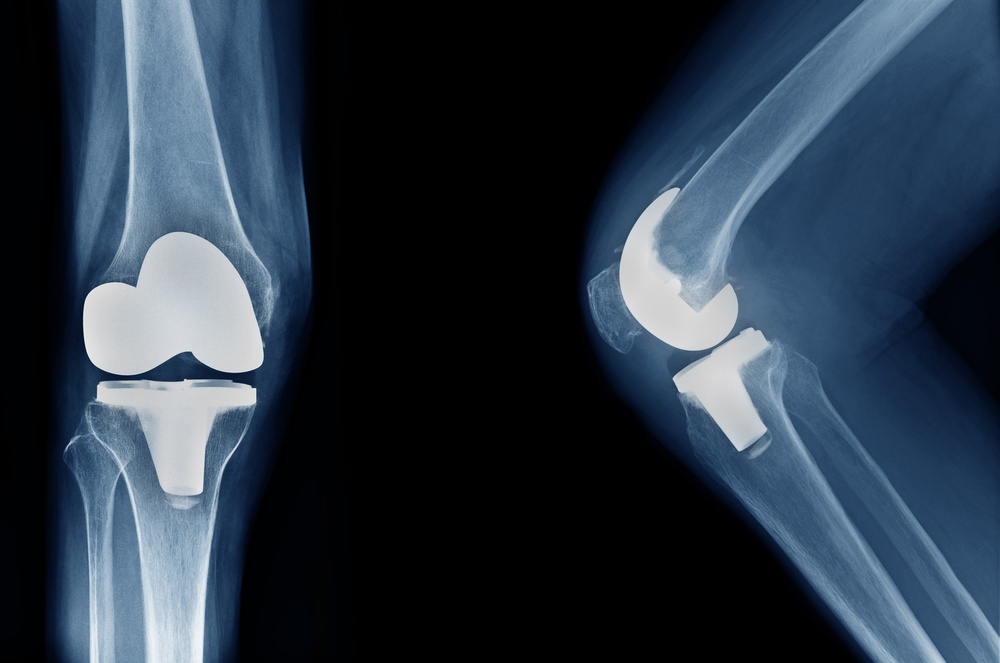

At VijaySheela Sports-Orthopedics Clinic, Bengaluru, Dr. Vijay Girish is highly experienced in performing Revision Total Knee Replacement — a complex surgical procedure done to replace or repair a previously implanted knee prosthesis that has failed due to wear, infection, loosening, instability, or mechanical issues. The goal of revision surgery is to restore proper joint function, eliminate pain, and ensure long-term stability of the knee joint.

Revision Total Knee Replacement is more intricate than the initial knee replacement, as it involves careful removal of the old implant, reconstruction of bone loss, and precise placement of the new prosthesis. With advanced surgical planning and state-of-the-art implant systems, patients can regain comfort, strength, and mobility for an improved quality of life.

Revision Total Knee Replacement is a surgical procedure performed when a primary knee replacement no longer functions properly. The surgery involves removing the damaged or loosened components and replacing them with specialized revision implants that offer better stability and support. It may also involve bone grafting to rebuild lost bone and ensure the new prosthesis fits securely. This advanced procedure helps restore alignment, relieve chronic pain, and enhance the overall biomechanics of the knee joint.